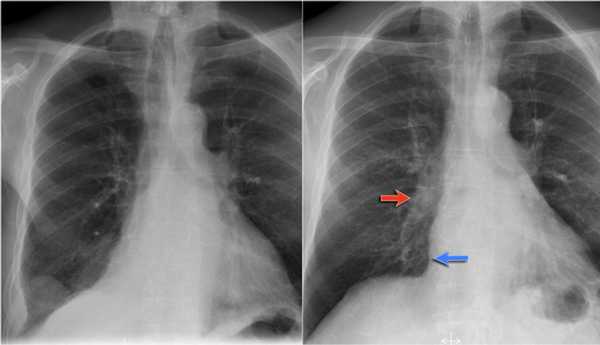

Ателектаз верхней доли правого легкого.

Оцените ниже лежащие изображения, а после продолжите чтение.

- Трехгранное затенение.

- Подъем правого корня легкого

- Облитерация загрудинного пространства (указано стрелкой).

На ПЭТ/КТ визуализируется опухоль легкого с обструкцией правого верхнедолевого бронха, как следствие ателектаз верхний доли правого легкого.

Также очень частым проявлением ателектаза является подъем диафрагмы, что хорошо визуализируется на ниже представленной рентгенограмме (указано синий стрелкой).

У данного пациента карцинома легкого с билатеральным метастазированием в легкие (указано красными стрелкам).

Обратите внимание на правую междолевую артерию (красная стрелка) и границы правых отделов сердца (синяя стрелка).